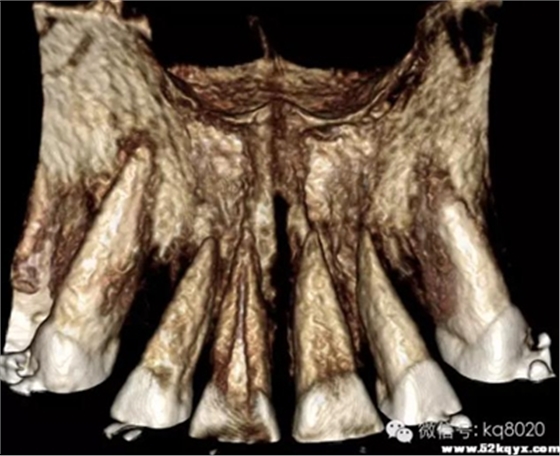

顴牙槽嵴(成人多在67之間,未成年多在56之間或6上方,根據(jù)CT確定)

危險(xiǎn)因素:此處植入容易穿破上頜竇底,植入角度需注意;骨質(zhì)較為堅(jiān)硬,支抗釘易折斷

植入位置和角度:在不滑脫的基礎(chǔ)上越平行于骨面越安全。要根據(jù)顴牙槽嵴的斜度決定植入角度,為避免滑脫,

可先垂直于骨面植入,在調(diào)整方向斜向上,一般植入角度向牙合面旋轉(zhuǎn)60°-70°

大?。河捎诖颂幑琴|(zhì)堅(jiān)硬,宜用10×2.0mm,且支抗釘尖端應(yīng)有切削頭設(shè)計(jì),以切削骨碎屑,利于植入腭側(cè)牙根之間